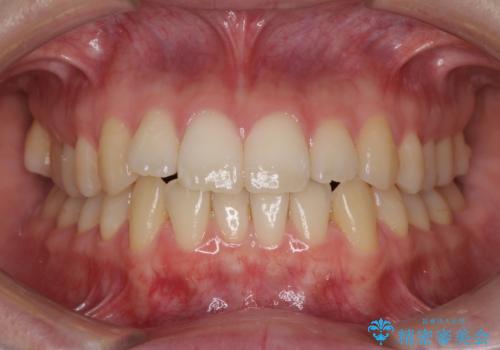

上下前歯の捻れが改善され、患者様には大変満足していただきました。